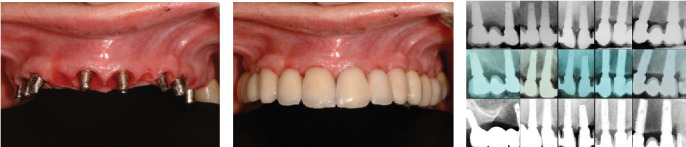

需要上颌种植体康复的部分义齿,无论是使用分段式还是夹板固定义齿,通常都需要进行三维牙位规划。这种规划可能导致牙冠边缘接触或侵蚀剩余的牙槽骨,这是以前的上牙疹的后果。上萌牙与牙周生长有关,牙周韧带和牙周骨与萌牙同时发育。在这种情况下,为了获得成功的结果,在植入假体之前进行骨重塑是至关重要的,为生物宽度创造足够的空间,这对于实现分段、种植体支持、固定的假体是必不可少的。在本病例报告中,患者接受了8个假体和4个固定部分假体,在使用假体18年后,种植体周围炎需要移除后路假体,需要在相应象限重新治疗。值得注意的是,假体之间的近端接触已经打开,可能是由于颅面继续生长和骨重塑,尽管这并不影响患者的功能。修复后的骨和软组织保持原位,近端间乳头和牙龈轮廓均保留在美观区。

Partial edentulism requiring maxillary rehabilitation with dental implants, whether using segmented or splinted fixed prostheses, often involves three-dimensional tooth position planning. This planning can lead to crown margins that either contact or encroach upon the remaining alveolar bone, a consequence of previous supraeruption. Supraeruption is associated with periodontal growth, where the periodontal ligament and bone develop concurrently with the erupting tooth. For successful outcomes in such cases, it is crucial to perform bone recontouring before implant placement, creating adequate space for the biological width, which is essential for achieving a segmented, implant-supported, fixed prosthesis. In the patient described in this case report, who received eight implants and four fixed partial prostheses, peri-implantitis required the removal of a posterior implant after 18 years of prosthesis use, necessitating retreatment in the corresponding quadrant. Notably, interproximal contacts between the prostheses had opened, likely due to continued craniofacial growth and bone remodeling, although this did not affect the patient's functionality. The recontoured bone and soft tissues maintained their position, preserving both the interproximal papillae and gingival contour in the esthetic zone.